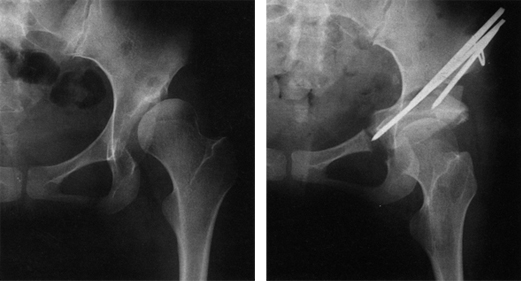

구제 절골술은 심한 변형이 있거나, 이미 관절염이 생겨 재형성 절골술을 시행하여도 정상적인 관절 접촉을 얻을 수 없는 경우에 비구를 확장시켜 대퇴골두를 좀더 덮어줌으로써 퇴행성 변화의 진행을 늦추고 인공관절수술시기를 연기하려는 목적으로 시행됩니다(그림3). 절골된 골편을 고정하고 원활한 골유합을 얻기 위해 나사못이나 핀, 혹은 금속판을 사용하여 고정하게 됩니다.

고관절 주위 절골술 이미지